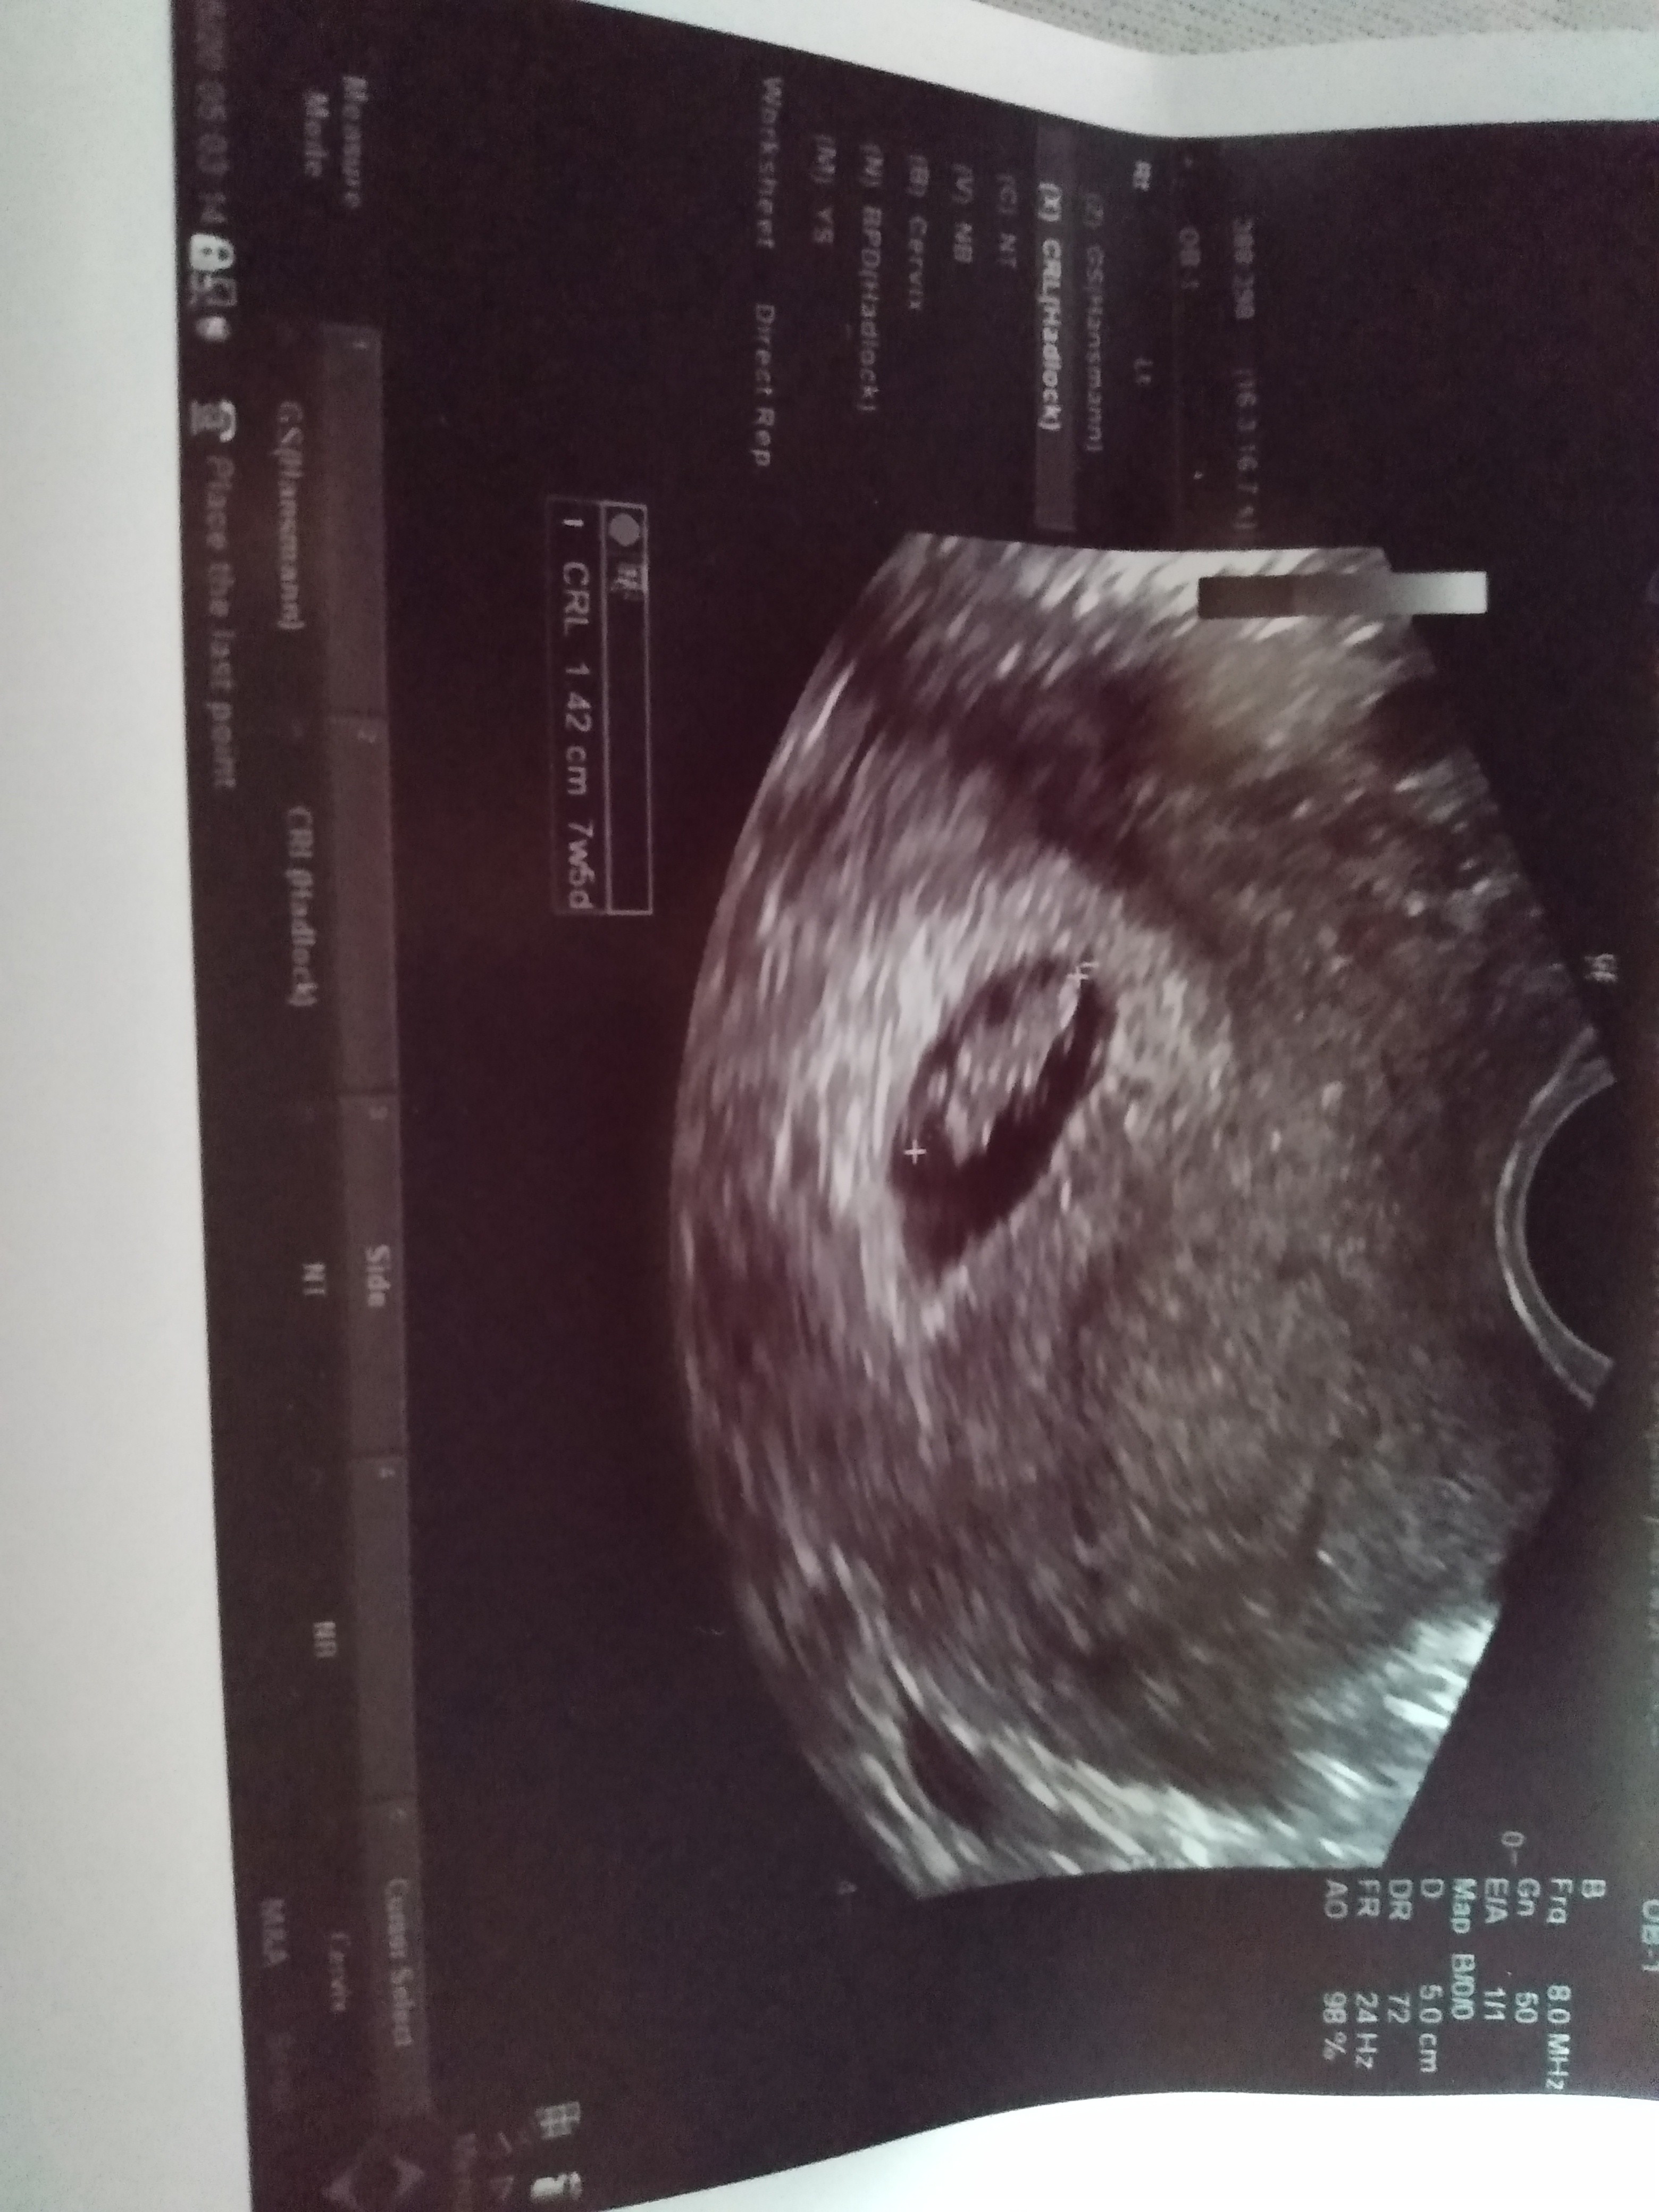

ja też dziś po wizycie, w końcu założona karta ciąży

11+0, termin na 7.12. Bobas wariował, machał rączkami i nie chciał dać się zmierzyć

w końcu się udało, 4,7 cm. Tętno 179 więc wychodzi na to że znowu dziewczynka? Nie wiem do kiedy się to bierze pod uwagę